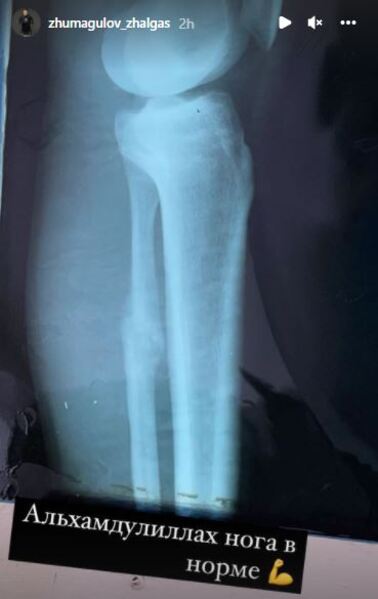

Известный казахстанский боец UFC Жалгас Жумагулов на своей странице в инстаграм поделился новостями о своей травмированной ноге, которую он в последнее время подвергал терапии и лечению, передает Sports.kz.

Жако сообщил, что его нога находится в полном порядке и не помешает ему вернуться в октагон. В данный момент казахстанец ожидает информацию о своем следующем поединке в UFC.